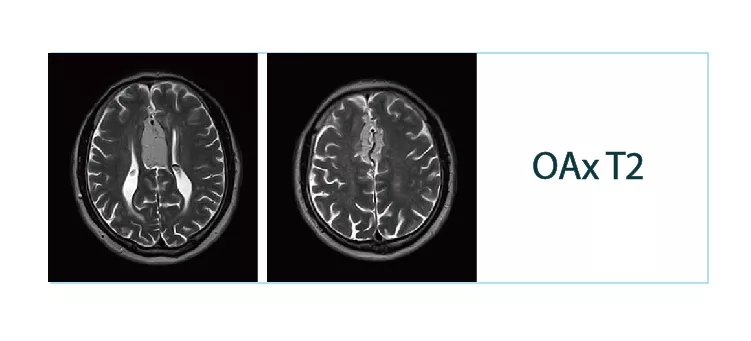

【朗润影像档案】20180511磁共振影像病例结果讨论